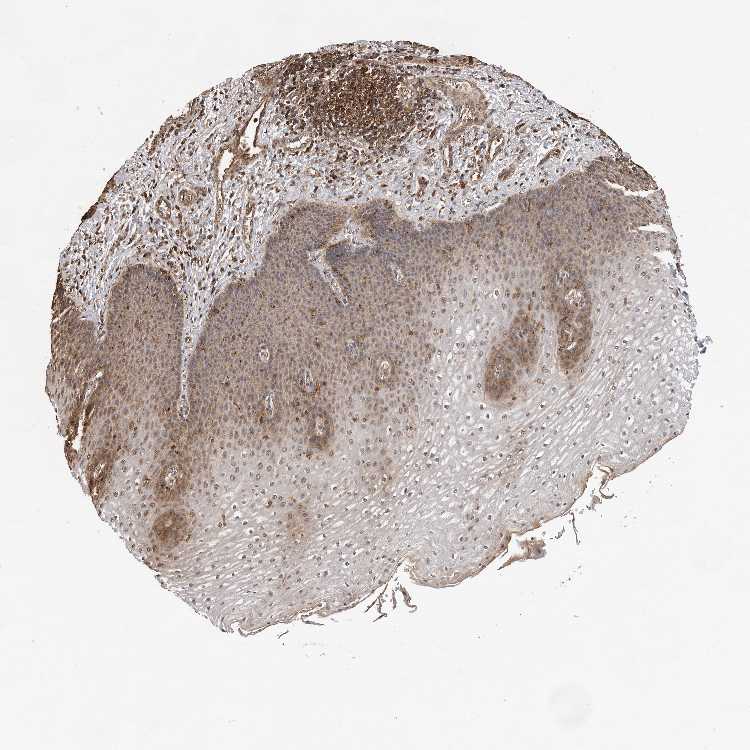

ESOPHAGUS - Antibody stainingi

Antibody staining in the annotated cell types in the current human tissue is reported as not detected, low, medium, or high, based on conventional immunohistochemistry profiling in selected tissues. This score is based on the combination of the staining intensity and fraction of stained cells.

Each image is clickable and will lead to virtual microscopy that enables deeper exploration of all samples and also displays staining intensity scores, fraction scores and subcellular localization as well as patient and tissue information for each sample.

Antibody HPA021854Antibody HPA021991Antibody HPA023922

Squamous epithelial cells MediumMediumMedium